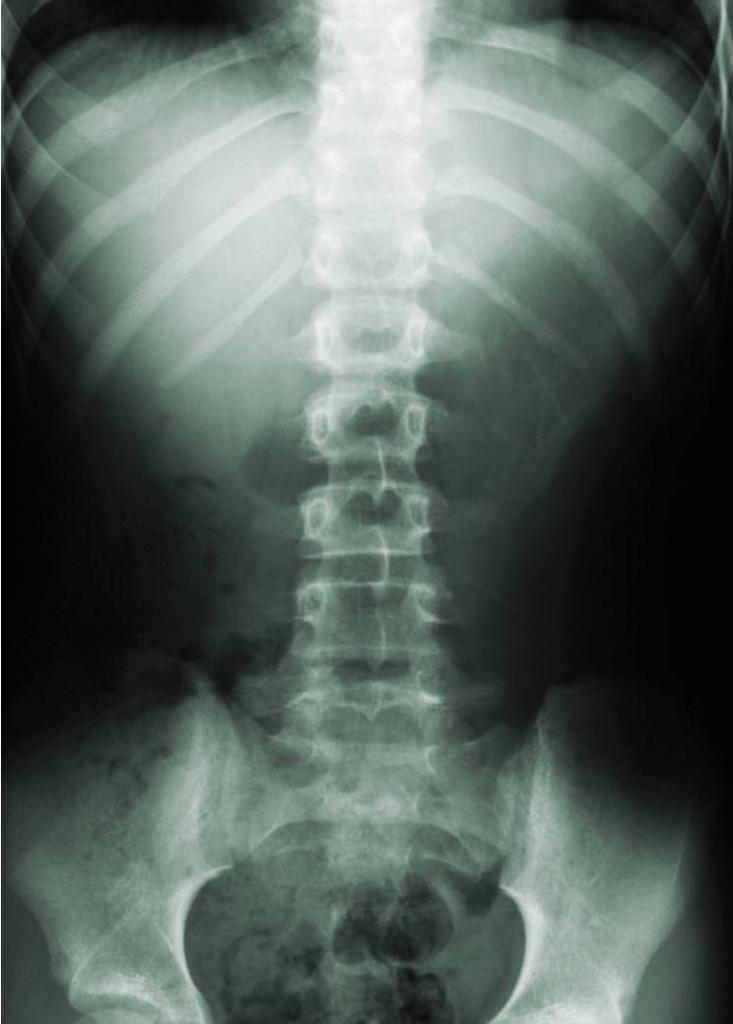

синяки на позвоночнике рентген

Диагностические мероприятия при синяках на позвоночнике, как у ребенка, так и у взрослого, сводятся к следующим действиям:

6. Рентгенография. Определит место повреждения и его характер.

7. КТ и МРТ более точно осветит картину происходящего, повреждение спинного мозга, позвонков и межпозвоночных дисков.